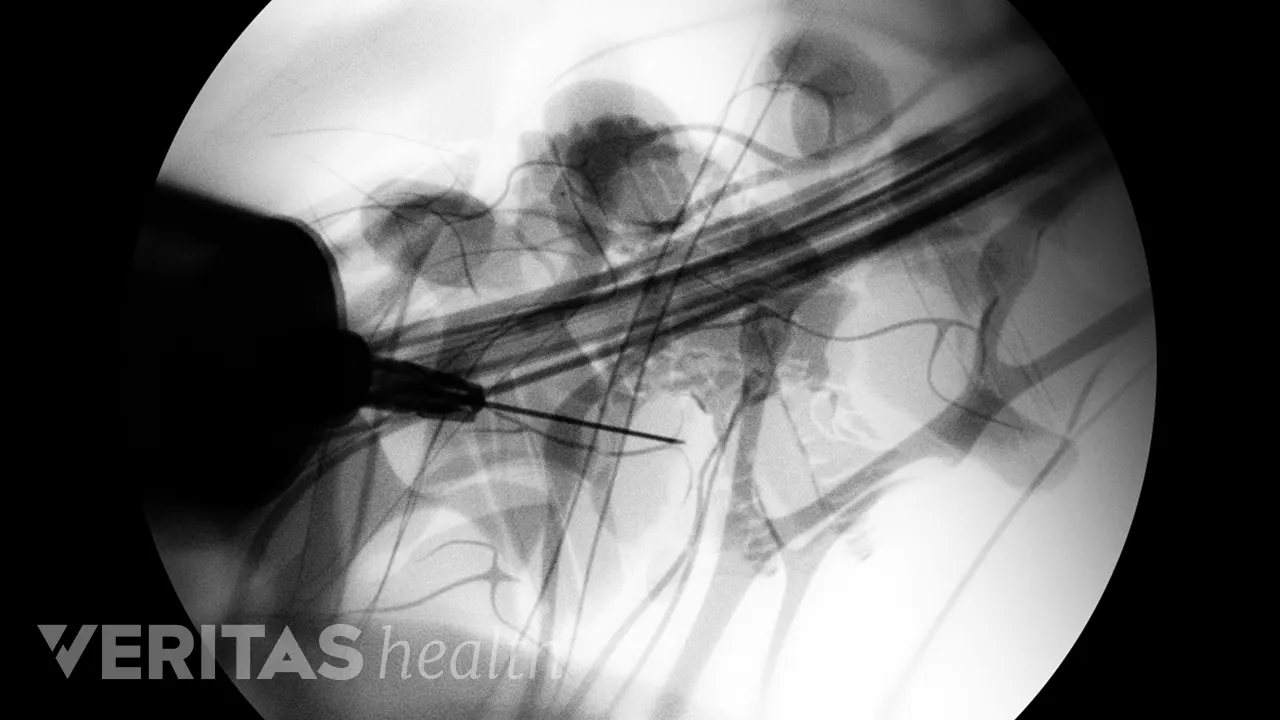

Next, the physician uses X-ray guidance, called fluoroscopy, to direct a small needle over the medial branch nerves. A small amount of contrast dye is injected to confirm that the medicine covers the medial branch nerve. Following this confirmation, a numbing medicine, called an anesthetic, is slowly injected onto each targeted nerve.